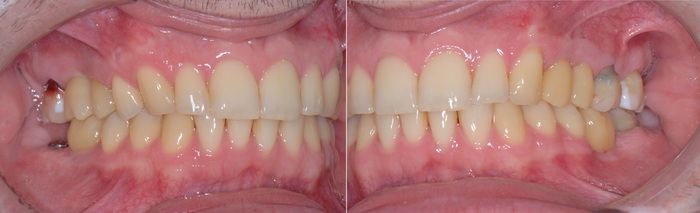

Я решил добавить фотографии сразу после снятия брекетов, а не с ними, как это было на рентгеновском снимке. Думаю, так выглядит намного симпатичнее.

Коронки страшненькие – на то они и временные. Такой тип коронок необходим для «доформирования контура десны» и для того, чтобы «ввести области в жевание» из-за длительного отсутствия зубов. Необходимо подготовить мышцы, связки, сустав, остальные зубы к нормальному жеванию. Временные коронки можно корректировать при необходимости.

Шло время. Так же молниеносно, как проходит молодость. Ещё 3 месяца и пора менять временные коронки на постоянные. Кстати, средний срок использования временных конструкций как раз 3-4 месяца. Почему? Как минимум, пластик истирается, как максимум, очень хорошо задерживает на себе еду и зубной налёт, что при хреновом уходе приводит к воспалению и проблемам.

В процессе лечения 7-ой зуб на нижней челюсти треснул, появился скол, пришлось от него тоже избавиться. Ниже снимок с постоянными коронками и «внеплановым» имлпантатом:

Вид «изнутри»:

Полость рта всё больше начинает преображаться.

Ещё один квантовый скачок и проходит 3.5 месяца. Выход на сцену временной коронки на имплантате, который был установлен позже остальных:

Вы её видите? И я не вижу. А она есть:

К моему великому сожалению, фотографии с финальным результатом у меня нет. Планировалось тотальное протезирование всех зубов и возможная замена постоянных коронок на имплантатах на другие, чуть более светлые.

По большому счету на фото изменится лишь цвет постоянных коронок на имплантатах и появятся керамические коронки того же цвета на своих жевательных зубах.